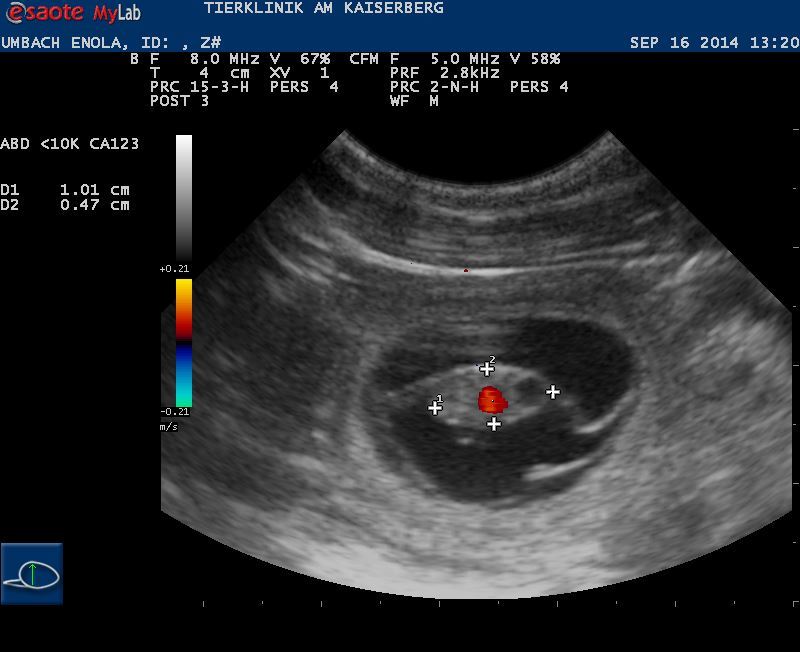

Am 16.09.2014 wurde die Trächtigkeit von Dr. Kresken / Tierklinik Kaiserberg, in Duisburg bestätigt

Ultraschallbild ( Beweisaufnahme)